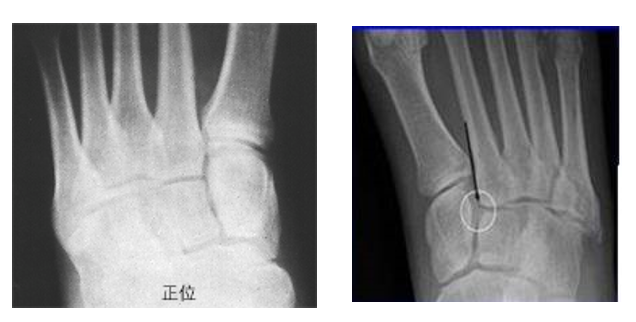

在足正位X线上,第1、2、3跖骨的内外侧缘分别和它相对应的楔骨的内外侧缘呈一直线排列;第一、二跖骨基底间隙和内中楔骨间隙相等。

30°斜位上:1、第四跖骨内侧缘和骰骨内侧缘连续成一条直线2、第三跖骨内侧缘和外侧楔骨内侧缘连续成一条直线3、第二、三跖骨基底间隙和内、中楔骨间隙相等。

侧位上,跖骨不超过相应楔骨背侧缘。从远端的跖骨经过跖跗关节到近端的跗骨,应该是一条不间断的连线

2005年Pearse等提出“ABC”的方法来阅读足部X 线片, 以减少中、前足的漏诊。 A ( alignment)检查跖骨与相应楔骨的对应线 B ( bone)检查每一块骨的轮廓 C ( congruity )检查整体一致吻合, 在正位片上观察内柱, 在斜位片上观察中、外柱。侧位片的常规检查可发现Lisfranc关节矢状面的半脱位及撕脱性骨折

Lisfranc损伤骨折复位标准:1、C形臂透视显示正、侧、斜位均为正常解剖复位2、如复位后第1、2跖骨基底间隙和内、中楔骨间隙<2mm,跖跗骨轴线<15°为近解剖复位,可以接受,超过这个范围的移位则无法接受3、复位好后,沿第一跖骨轴线向内侧楔骨逆行拧入一枚4.0mm皮质骨螺钉。螺钉由关节远侧1.5-2.0cm处进入,平行于足底或略向跖侧。